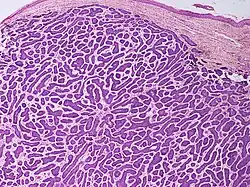

Nodular basal-cell carcinoma

.jpg)

Nodular basal-cell carcinoma (also known as "classic basal-cell carcinoma") accounts for 50% of all BCC.[29] It most commonly occurs on the sun-exposed areas of the head and neck.[30]: 748 [31]: 646 Histopathology shows aggregates of basaloid cells with well-defined borders, showing a peripheral palisading of cells and one or more typical clefts.[29] Such clefts are caused by shrinkage of mucin during tissue fixation and staining.[32] Central necrosis with eosinophilic, granular features may also be present, as well as mucin. The heavy aggregates of mucin determine a cystic structure. Calcification may also be present, especially in long-standing lesions.[29] Mitotic activity is usually not so evident, but a high mitotic rate may be present in more aggressive lesions.[29] Adenoidal BCC can be classified as a variant of NBCC, characterized by basaloid cells with a reticulated configuration extending into the dermis.[29]